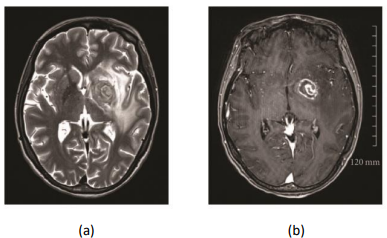

(a) Sequência em T2 demonstrando sinal de alvo “concêntrico” com alternância de aros concêntricos hiperintensos e hipointensos; (b) Sequência pós-contraste em T1 demonstrando sinal de alvo “excêntrico” com aro periférico de captação de contraste e nódulo focal lateral esquerdo com realce excêntrico.